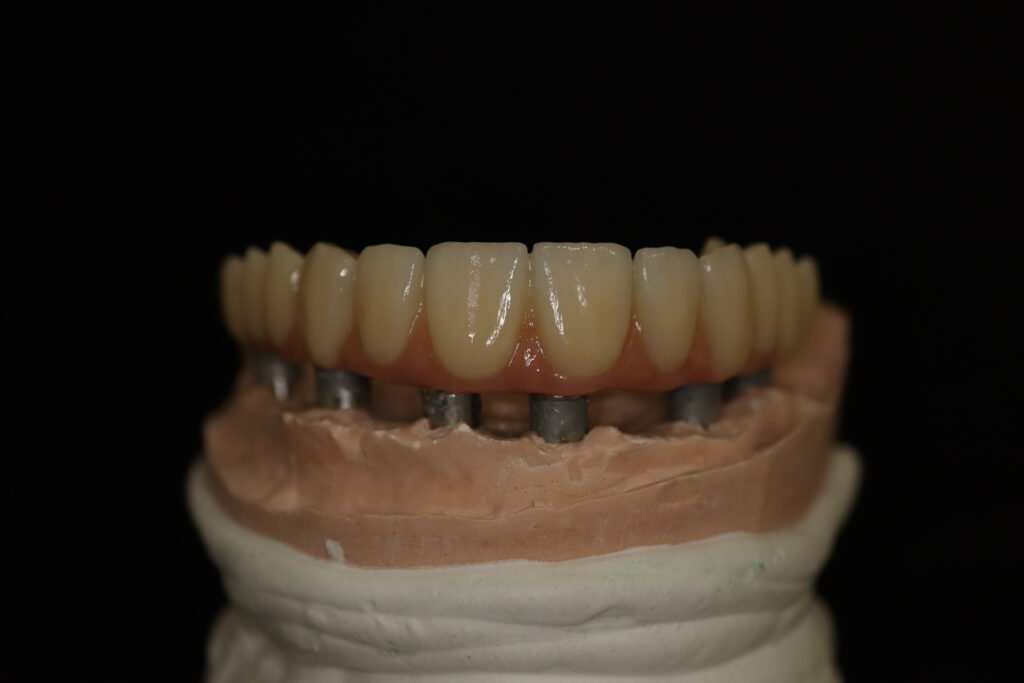

На консультации было принято решение о перепротезировании протезом из диоксида циркония на титановой балке.

Спустя 27 дней был зафиксирован протез с опопрой на дентальные имплантаты из диоксида циркония с каркасом из титана.

Пациенту были установлены 6 имплантатов Megagen AnyOne по системе All-on-6 на верхней челюсти и 4 имплантата на нижней по классической двухэтапной методике.